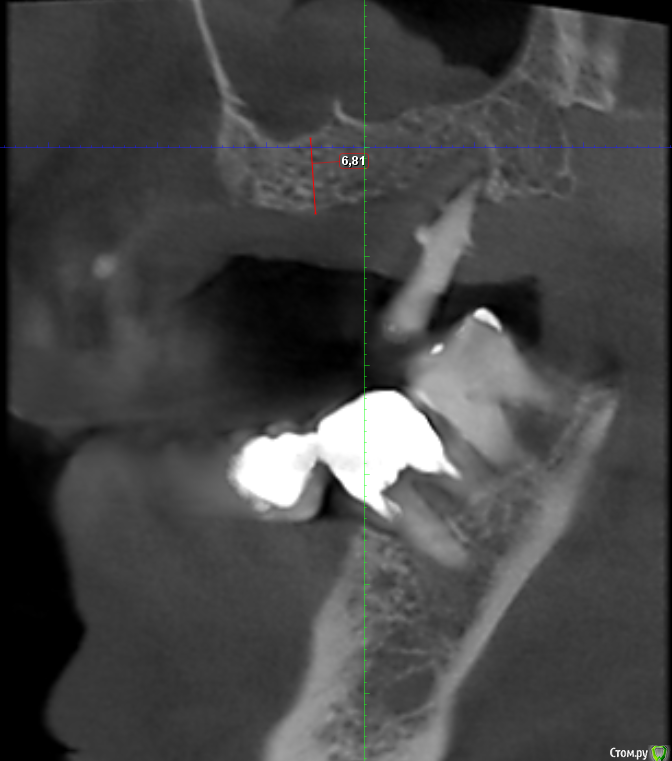

Serg2018 Опубликовано 28 ноября, 2018 Автор Поделиться Опубликовано 28 ноября, 2018 Вот пытаюсь выложить несколько срезов КТ правой стороны, надеюсь, я это правильно понял, делаю впервые. Также тыкал мышкой и она мне что-то замеряла, если в мм, то получается, что в самой тонкой части толщина 2,8 мм? или это я все неправильно понимаю? Ссылка на комментарий

Nazim_NV86 Опубликовано 28 ноября, 2018 Поделиться Опубликовано 28 ноября, 2018 (изменено) Sirona Galileos ?Должно быть окно, где срезы видны как распил. Сечение. Лучше на этом измерять. Можете всю томограмму загрузить на яндекс диск и выложить ссылку. Но сначала проверьте как работает запуск. На той программе, что выше написал, запуск скорее всего возможен только с диска. Если среди файлов на диске есть файл DCM, то его одного достаточно. Просмотрщик не нужно выкладывать. Изменено 28 ноября, 2018 пользователем Nazim_NV86 Ссылка на комментарий